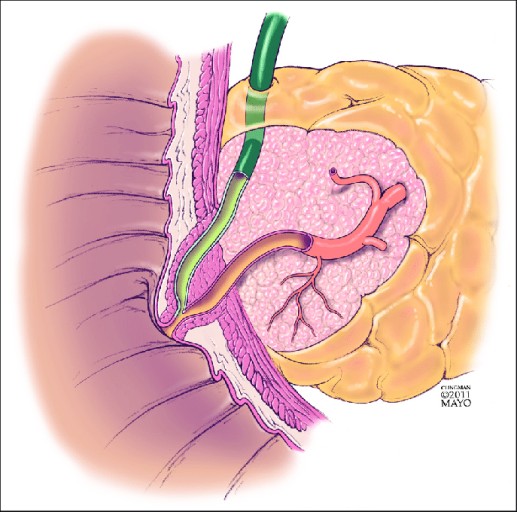

췌장염 증상 황달 + 진한 소변 + 연·회색 변(담즙 배출 장애 신호)

췌장과 담도는 해부학적으로 가깝습니다. 염증/부종이나 담석이 담즙 흐름을 막으면 피부·눈 흰자 노랗게(황달), 소변 짙은 갈색, 변이 옅거나 회색으로 바뀔 수 있습니다